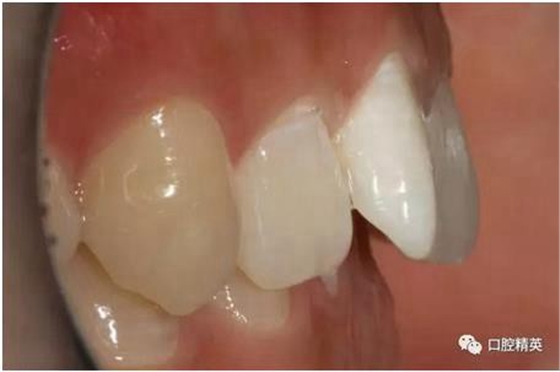

口內(nèi)正側(cè)位及切端特寫(xiě)

從側(cè)位照可看出遠(yuǎn)中切角略有回收